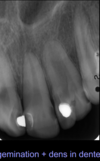

Define gemination

Division of a tooth bud of a single tooth --\> normal number of teeth on the arch Deciduous \> permanent Important to examine radiographically to reveal extent to decide on management

38

3 forms of gemination

* One large crown * Crown divided by a groove * 2 crowns with pulp chamber can be enlarged, but single, partially divided

Define fusion

Fusion of 2 teeth --\> reduced number of teeth on the arch. Important to examine radiographically to reveal extent of fusion and decide on management

36

4 forms of fusion

* One large tooth * Bifid crowns with one root * 2 teeth united by dentin * Rarely, 2 teeth united by enamel